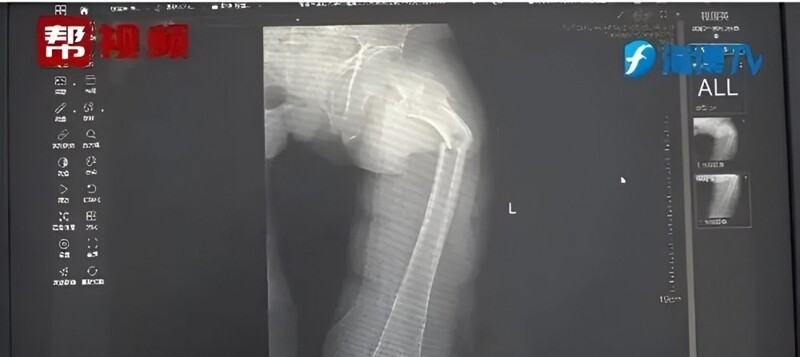

Doctors from the Second People's Hospital of Fujian Province examined the leg, took an x-ray just in case, and found out that the leg hurt due to a fracture of the femur. They began to find out how the guy broke it, asked about his general health, eating habits and lifestyle, and also conducted a bone density test, which gave alarming results.

The bone density was the same as that of an 80-year-old man, which was unusual even for modern sedentary men.